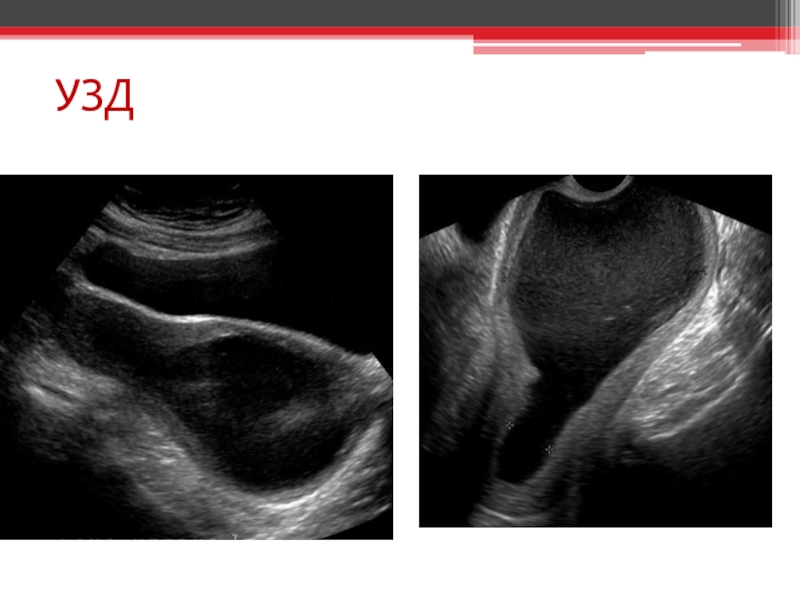

При огляді гіменоскопом виявляється випинання назовні дівочої пліви синюватого кольору

Ректоабдомінальне дослідження ділянки вагіни виявляє пухлиноподібне еластичне утворення

Атрезія дівочої пліви. Гематокольпос. Гематометра. Гематосальпінкс. Гострий місцевий перитоніт. Гостра затримка

сечі. Гідрокалікоз.